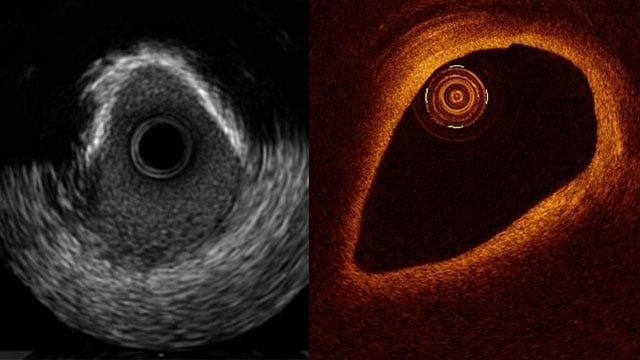

A range of resources, content and events dedicated to imaging for imaging specialists, interventional cardiologists and teams committed to the management of coronary artery disease.

In this section you will find a range of resources dedicated to imaging built for imaging specialists, interventional cardiologists and teams committed to the management of patients who need coronary, valvular or structural interventions. These resources can contribute to your diagnosis and treatment skills to improve patient care before, during and after intervention.